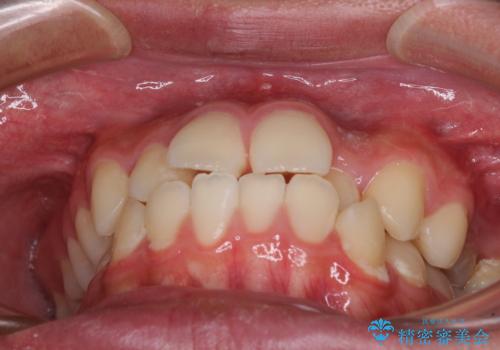

- 前歯のデコボコと口元の突出感を気にして来院された患者様です。

上下前歯がくちばしのように突出していたため、上下左右の第一小臼歯4本を抜歯し、ワイヤー装置にて矯正治療を行うこととしました。

第二小臼歯抜歯により治療期間が長くなることを了承いただき、治療を開始しました。

上顎骨に対して下顎骨がやや前方位に位置しているため、下顎前歯をあまり内側に移動させることができず、口元の突出感改善は期待以上にはならないと予測しておりましたが、満足いくの引っ込み具合となりました。